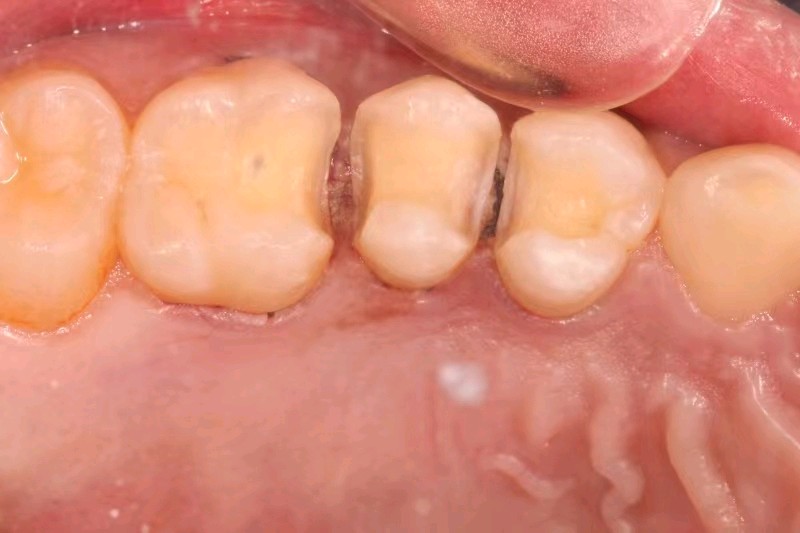

患者女,三十五岁。主诉右上后牙食物嵌塞。检查发现14、15、16邻面龋坏,色泽发黑,质硬冷测正常,余无特殊。治疗计划:去腐后嵌体修复。

食物嵌塞为细菌提供了良好的滋生环境,容易导致细菌大量繁殖,产生酸性物质,从而增加蛀牙的风险。最好是用嵌体修复,能更好的恢复牙体的形态和功能。想要有一口好牙齿,做起来也不难。但是,单单口腔清洁这件小事,大多数人都没做好。你以为刷遍了牙齿的每个角落,但可能只刷了一半的牙。刷毛无法有效进入牙缝隙刷牙后仍有食物残渣等残留于牙齿邻面部位导致邻面龋坏。平时不易察觉,需要定期检查,为了更恢复邻接关系,预备制作嵌体,更好的恢复了牙体形态,增加了固位力,恢复正常的邻接关系,可以得到洁。基牙预备后,通过德国西诺德 CER 日完成即可佩戴,患者满意。